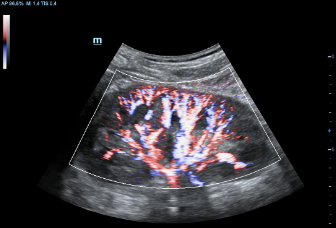

–ú–Ĺ–ĺ–≥–ĺ—Ą—É–Ĺ–ļ—Ü–ł–ĺ–Ĺ–į–Ľ—Ć–Ĺ–į—Ź —Ā–ł—Ā—ā–Ķ–ľ–į DC-60 Exp —Ā X-Insight –Ņ—Ä–Ķ–ī—Ā—ā–į–≤–Ľ—Ź–Ķ—ā —Ā–ĺ–Ī–ĺ–Ļ –ļ–ĺ–ľ–Ņ–Ľ–Ķ–ļ—Ā–Ĺ–ĺ–Ķ —Ä–Ķ—ą–Ķ–Ĺ–ł–Ķ, –ļ–ĺ—ā–ĺ—Ä–ĺ–Ķ –Ņ–ĺ–ľ–ĺ–≥–į–Ķ—ā —É–Ņ—Ä–į–≤–Ľ—Ź—ā—Ć –Ņ–ĺ–≤—Ā–Ķ–ī–Ĺ–Ķ–≤–Ĺ–ĺ–Ļ –ļ–Ľ–ł–Ĺ–ł—á–Ķ—Ā–ļ–ĺ–Ļ –Ņ—Ä–į–ļ—ā–ł–ļ–ĺ–Ļ —Ā –Ľ–Ķ–≥–ļ–ĺ—Ā—ā—Ć—é –ł —É–≤–Ķ—Ä–Ķ–Ĺ–Ĺ–ĺ—Ā—ā—Ć—é.

–ě—Ā–Ĺ–ĺ–≤—č–≤–į—Ź—Ā—Ć –Ĺ–į –≥–Ľ—É–Ī–ĺ–ļ–ĺ–ľ –Ņ–ĺ–Ĺ–ł–ľ–į–Ĺ–ł–ł –Ņ–ĺ—ā—Ä–Ķ–Ī–Ĺ–ĺ—Ā—ā–Ķ–Ļ –ļ–Ľ–ł–Ķ–Ĺ—ā–ĺ–≤, –ļ–ĺ–ľ–Ņ–į–Ĺ–ł—Ź Mindray —Ä–į–∑—Ä–į–Ī–ĺ—ā–į–Ľ–į —Ā–ł—Ā—ā–Ķ–ľ—É DC-60 Exp —Ā X-Insight, —á—ā–ĺ–Ī—č –ĺ–Ī–Ķ—Ā–Ņ–Ķ—á–ł—ā—Ć –≤—č—Ā–ĺ–ļ—É—é –Ņ—Ä–ĺ–ł–∑–≤–ĺ–ī–ł—ā–Ķ–Ľ—Ć–Ĺ–ĺ—Ā—ā—Ć –ł —ā–ĺ—á–Ĺ–ĺ—Ā—ā—Ć –≤–ł–∑—É–į–Ľ–ł–∑–į—Ü–ł–ł –≤–ļ—É–Ņ–Ķ —Ā –Ĺ–į–≥–Ľ—Ź–ī–Ĺ–ĺ—Ā—ā—Ć—é, –ł—Ā–ļ–Ľ—é—á–ł—ā–Ķ–Ľ—Ć–Ĺ–ĺ–Ļ –ł–Ĺ—ā–Ķ–Ľ–Ľ–Ķ–ļ—ā—É–į–Ľ—Ć–Ĺ–ĺ—Ā—ā—Ć—é –ł –ĺ–≥—Ä–ĺ–ľ–Ĺ—č–ľ –ĺ–Ņ—č—ā–ĺ–ľ.